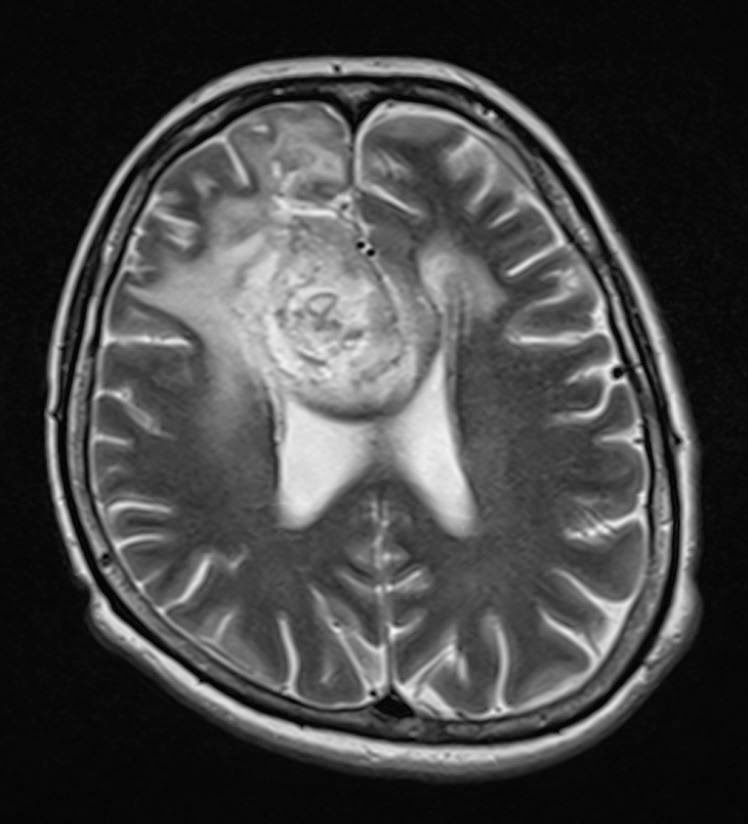

Összehasonlítva a 2014.02.10-i MR vizsgálattal:

A középvonalat balra kb. 1,5 cm-rel meghaladó és a corpus callosumot involváló jobb oldali frontalis inhomogén szerkeszetű és halmozású elváltozás mérete minden irányban mérsékelten csökkent, legnagyobb átmérője jelenleg kb. 5,6 x 5 x 4,7 cm. T2 súlyozásnál a laesio körül a hyperintenzitás kiterjedése főként dorsalis irányban enyhén csökkent. Az elülső frontalis műtéti behatolás mögött parasagittalisan a liquorhoz viszonyítva magasabb jelű bennéket tartalmazó cystosus elváltozás mérete hasonló a korábbihoz. Bal oldalon temporalis DVA* látható. A kamrarendszer frontális részeinek compressioja és dislocatioja lényegesen nem változott.

Vélemény: Enyhe méretcsökkenést mutató jobb túlsúlyú bifrontális tu. a corpus callosum infiltratiojaval.

*DVA: developmental venous anomaly (DVA) = cerebral venous angioma

Fejlődési eredetű (embrionális) vénás anomális = agyi vénás angióma (érdaganat)

Elkészült a kemoterápia alatti első MR-felvétel, és íme az eredménye:

Saját, műkedvelő fordításomban ez azt jelenti, hogy:

Jobb oldalon a corpus callosum, azaz kérgestest, amely nem más, mint a két agyféltekét összekötő rostköteg, és a gyrus cinguli, azaz az agyféltekék mediális, tehát középen elhelyezkedő felszínén található hosszú hajlított struktúra elülső részében elhelyezkedő térfoglalás nagysága érdemben nem változott, azonban a szélei jobban elhatárolódtak.

A mérsékelt fokú (hoppá! csak mérsékelt!!!) baloldali terjedés és a környező részben ödémás terület olyan, mint november 11-én volt. Az elülső és a frontális szarvak jobbra, lefelé nyomódtak össze. Továbbá az elülső szarvak hátsó fele olyan, mint volt: mérsékelten tágultak jobb túlsúllyal.

Ami jó hír: mérséklődött a középvonal balra íveltsége.

Mindazonáltal a jobb oldali árkok jobban ábrázolódnak.

A műtéti üreg a korábbihoz hasonló! Nem nőtt tovább a rohadék!!!

Az orvosi vélemény: Stabil állapot.